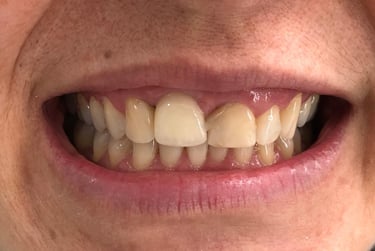

Coroas em Dissilicato de Lítio

Todos os caso a seguir estão associadas a clareamento dentário

Antes

Depois